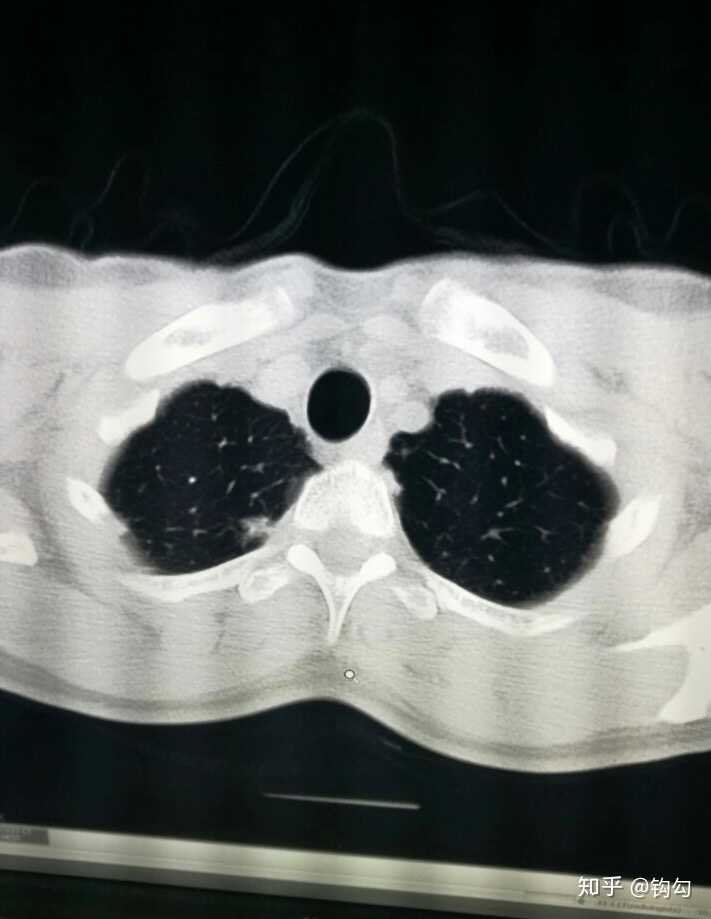

ct时在左上肺发现了一长串的纤维灶,毕竟是出现在癌中之王的肺部里